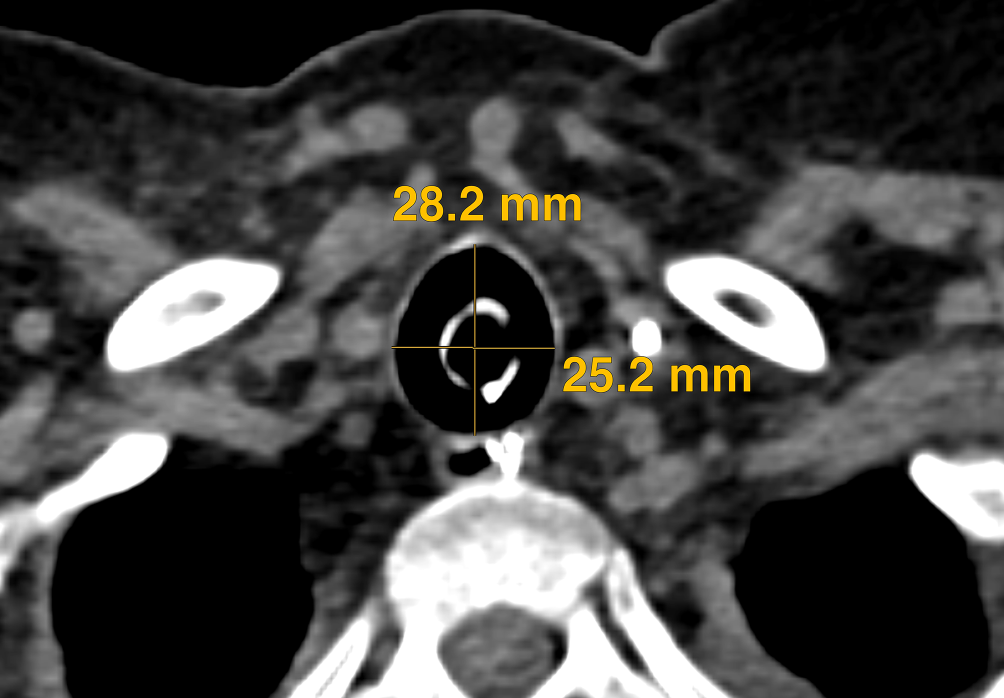

Abb. 1

Computertomographie des Thorax mit Messung der anterior-posterioren und horizontalen Trachealdurchmesser